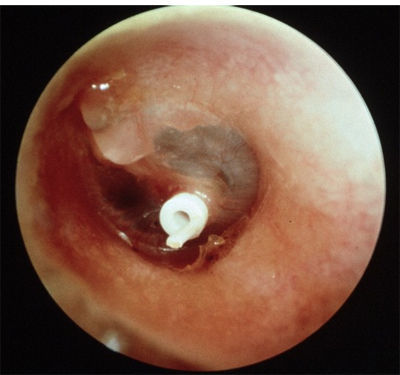

Question 8

Question

Function of the object in the TM

5998cfbe-2eb7-4a5e-b0c2-fba93d0d5a41 (image/jpg)

Answer

To drain the pus

Extrudes in about 6-9 months

Used to treat glue ear